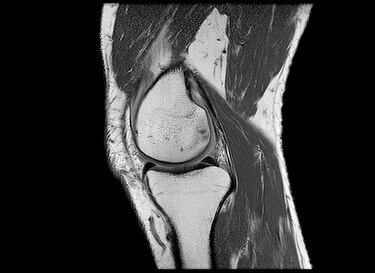

“La rodilla es una de las articulaciones más complejas de todo el cuerpo”, le dice a la BBC Anikar Chhabra, un cirujano ortopédico especializado en medicina deportiva de la Clínica Mayo en Phoenix, Estados Unidos.